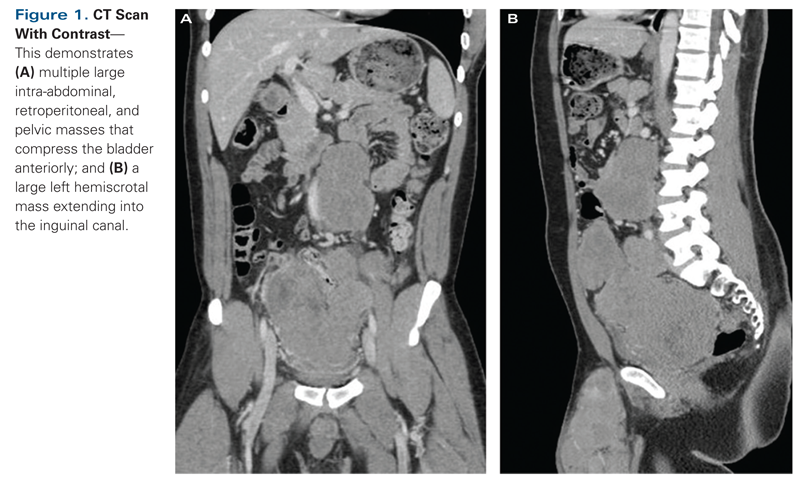

Figure 1. CT Scan With Contrast

Laboratory results, including results of a complete blood cell count with differential, liver function tests, coagulation panel, and basic chemistry panel, were unremarkable except for a serum creatinine level of 2.6 mg/dL. Typical markers for a testicular germ cell tumor were within normal limits: the beta–human chorionic gonadotropin level was less than 1 mIU/mL and the alpha fetoprotein level was less than 2.8 ng/mL. A CT scan of the chest, abdomen, and pelvis with intravenous contrast was obtained, and it showed large multifocal intra-abdominal, retroperitoneal, and pelvic masses (Figure 1). On cross-sectional imaging, a 7.8-cm para-aortic mass was visualized compressing the proximal portion of the left ureter, creating moderate left hydroureteronephrosis. Additionally, three separate pelvic masses were present in the retrovesical space, each measuring approximately 5 to 10 cm at their largest diameter; these displaced the bladder anteriorly and the rectum posteriorly.